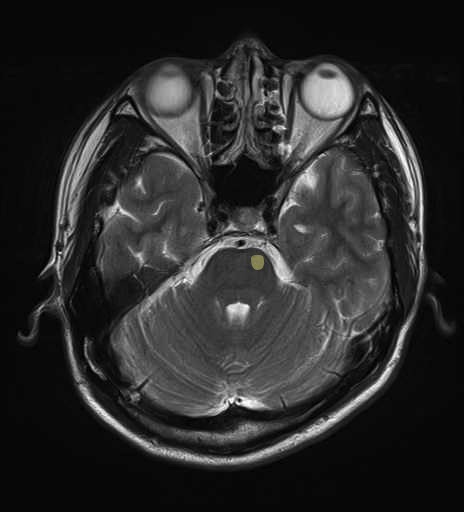

運動系 錐体路系に色を付けました。

■皮質核路:一次運動野から橋及び脊髄神経核まで